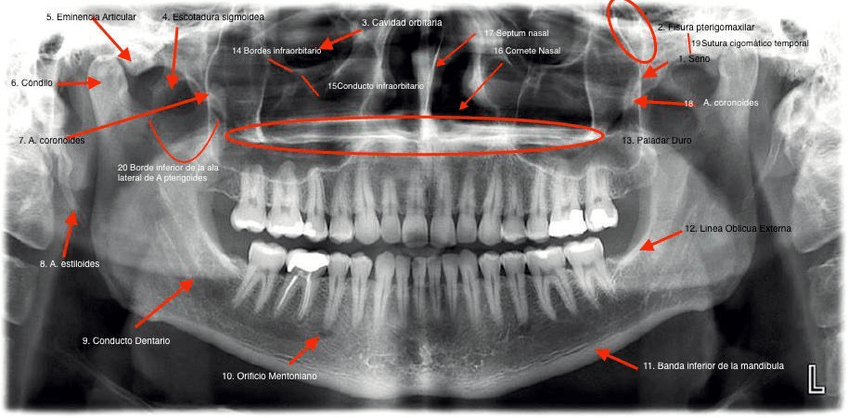

IMÁGENES

He publicado nuevos apuntes de 2º Radiología bucal: IMÁGENES

Con-letra.jpg

Sin-letra.jpg